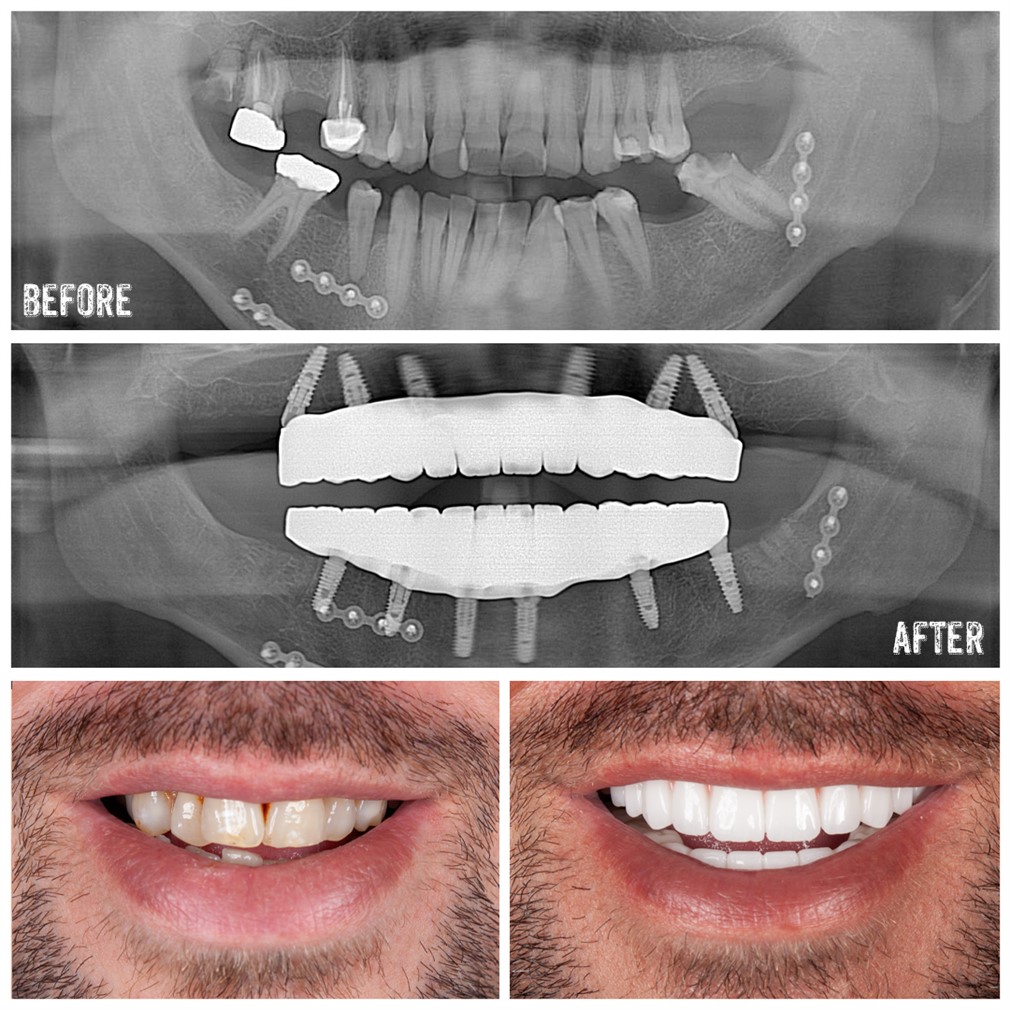

All-on-4 treatment, which has become quite popular in modern dentistry, offers many advantages for patients as an implant treatment method. This treatment option is faster, more economical, and more effective compared to traditional implant treatments, especially for patients who are completely edentulous or at risk of becoming completely edentulous in the near future.

Implantation is one of the methods developed to replace lost teeth due to chewing, taste perception, speech, pain, and aesthetics. However, implant treatment tends to be more prolonged and costly for patients who are completely edentulous or at risk of becoming completely edentulous in the near future. All-on-4 treatment is a rapid and effective treatment method aimed at eliminating the need for advanced surgery due to sinus lift, bone addition, and insufficient bone in patients who are completely edentulous.

The All-on-4 treatment concept involves the fixed full-jaw prosthetic restoration on 4-6 implants placed in the same surgical operation. Considering function, aesthetics, taste, speech, and confidence, it ensures patient satisfaction.

The All-on-4 treatment utilizes the titanium screw mechanism used in traditional implants. The most significant difference between traditional implants and All-on-4 implants lies in how they are positioned within the mouth. While 8 or 10 implants are typically used to replace missing teeth in a completely edentulous jaw, this new technique requires only 4 implants.

In the anterior region, 2 implants are placed where the bone is thickest, while in the posterior part of the jaw, 2 implants are placed. The implants in the front are positioned at a 90-degree angle, while those in the back are placed at a 45-degree angle to maximize strength. After these 4 implants are placed, bridges or crowns are fitted onto them.

Temporary prostheses are prepared based on measurements taken from patients before the All-on-4 treatment. If there are any teeth to be extracted, they are removed under local anesthesia, and the implants are placed. Temporary prostheses prepared based on measurements are then attached to these implants. After 3 months, the patient's permanent prostheses are fitted.